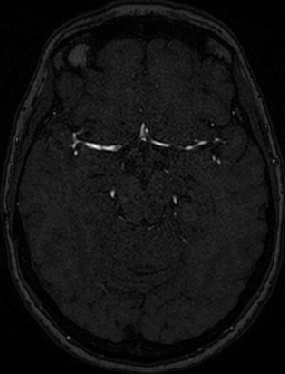

4.4 Qualitative Results

We show sample visual results of representative slices in Figure 3. Sample 3D visual results are given as surface renderings of segmentation maps in Figure 4.

The sGAN relies on the recent popular PatchGAN framework as the baseline. In the adaptation of the baseline method to MRA generation, the steerable-filter response based loss term included in the sGAN method highlights the directional features of vessel structures. This leads to an enhanced smoothing along vessels while improving their continuity. This is demonstrated qualitatively through visual inspection. In quantitative evaluations, the sGAN performs similarly with a slight increase (statistically insignificant) in PSNR values compared to those of the baseline. However, it is well-known that PSNR measure does not necessarily correspond to perceptual quality in image evaluations [20, 23]. In terms of the vascular segmentation maps extracted from the generated MRAs and the original MRA, the sGAN improves the overlap scores by against the baseline. This is a desirable output, as the MRA targets imaging of vascular anatomy.